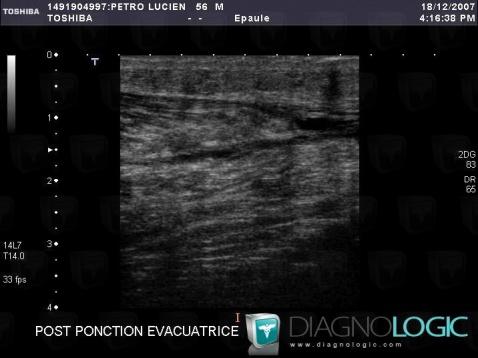

Tennis leg , Muscles - Leg, US

Here is the specific information in the key image above:

- Diagnosis Tennis leg , Location(s) Muscles - Leg, with gamuts